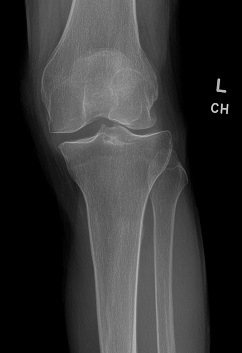

An 80 year old female presents to your office with a left ring finger deformity after a fall one week ago. She initially went to urgent care and xrays were unremarkable for a fracture (Figures 1 and 2). A photo of her left ring finger is shown in figure 3. On physical exam the left ring finger is in hyperextension at the PIP joint and flexion at the DIP joint. She able to flex her PIP joint with full motion. What is the best treatment option?